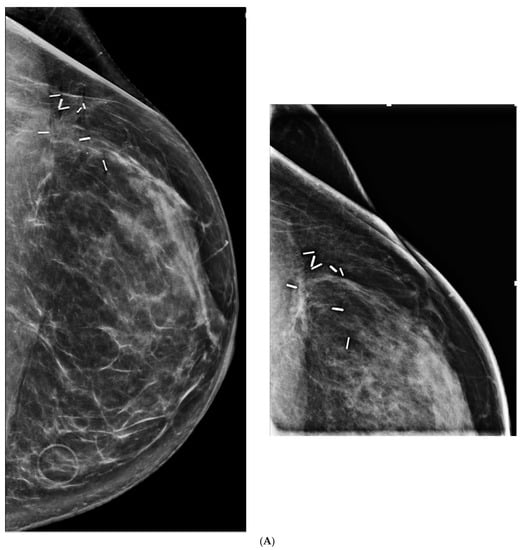

5. Ultrasound (US)